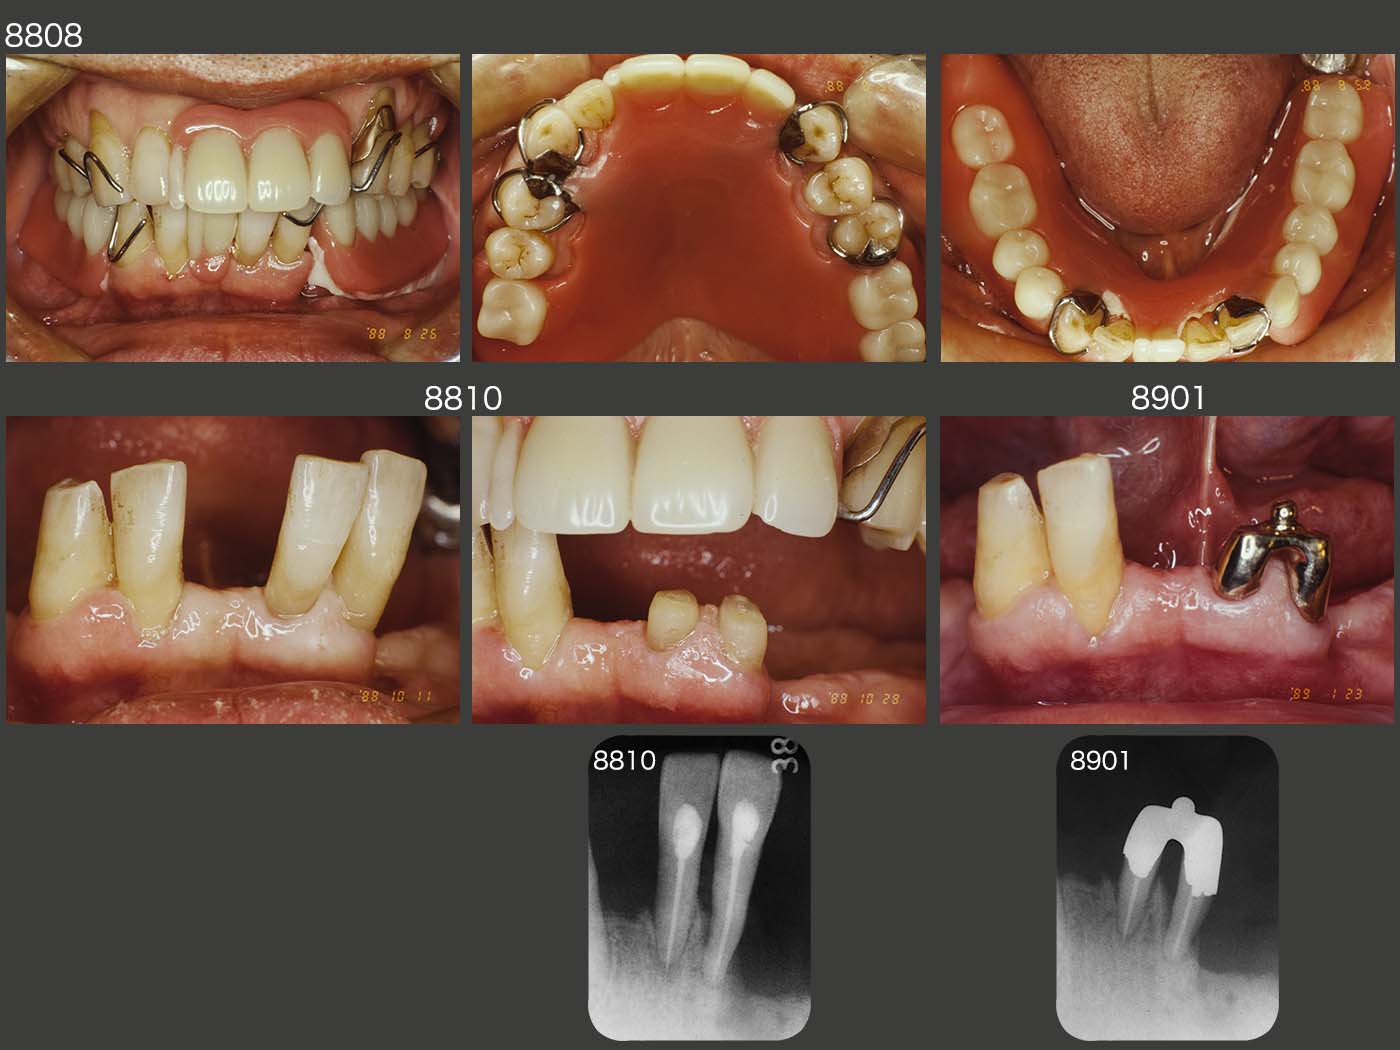

保存不可能な歯の抜去後,上下に暫間義歯を装着した.この時は右側の上下2,3が咬合しており下顎位は正しいと思われる.

左下1,2の歯周ポケットは最大5mmであったが,歯の動揺が著しく大きく,治療方針をどうするか悩んだ.最終的には抜髄し,着力点を下げることで歯の動揺を抑えようと目論んだ.また,たまたま根管の平行性が得られたので,連結固定した根面板にアタッチメントを付与し,歯の動揺をさらに少なくした.(今なら,抜髄せず,舌側に3/4冠を装着し連結固定すると思う.それでも歯の動揺が収まらなければ,右下2,3を含めて連結固定すると思われる.)

1989年6月,初診終了時の状態.左下2の近心に6mmの歯周ポケットが存在したが,ここ以外は5mm以内に収まった.アタッチメントはBona 604Aを用いた.なお,根面板を連結固定してアタッチメントを付与した症例は,後にも先にもこのケース1例だけである.

初診終了時の義歯を装着した状態.左下の根面アタッチメントの支台歯辺縁歯肉を開放し,唾液による自浄性の向上を図った.

さて,ここで大変なミスを犯してしまった.それは,右下2および3に切端レストを付与してしまったことである.すなわちこの分,咬合が挙上してしまった.(言い訳になるが,右上3,4間が空いていることから,右下3の突き上げで,右上3がフレアーアウトしたと考えれば,咬合が少し低くなっていたとも考えられる.そこで切端レスト分咬合を高くしたという屁理屈も成り立つ.しかし,長い年月をかけて徐々に下がった咬合を昔に戻してはいけないと今は考えている.)咬合を挙上すると,一般的には咬合力が強くなってしまう傾向がある.特に咬合力が元々強い人の咬合を挙上してしまうことは,さらに咬合力が増してしまうので大変危険である.

上段の写真は1995年8月,初診終了後6年2ヶ月の状態であるが,生体は残存歯の動揺,人工歯の摩耗,義歯床下の顎堤の吸収等を伴い,安定する咬合の高さに戻ろうとする性質をもっている.その結果として,切端レストの破損が生じたものと思われる.

2000年5月,左下アタッチメント装着歯の動揺が著しく増加し,痛みが出るようになったため抜去した.それでも,アタッチメントを装着して11年4ヵ月機能してくれた.